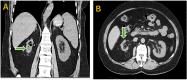

Figure 4. Follow-up CT of the kidneys showing right renal atrophy. (A) Coronal section: Green arrow indicates the atrophic right kidney. (B) Axial section: Green arrow highlights the atrophic right kidney.